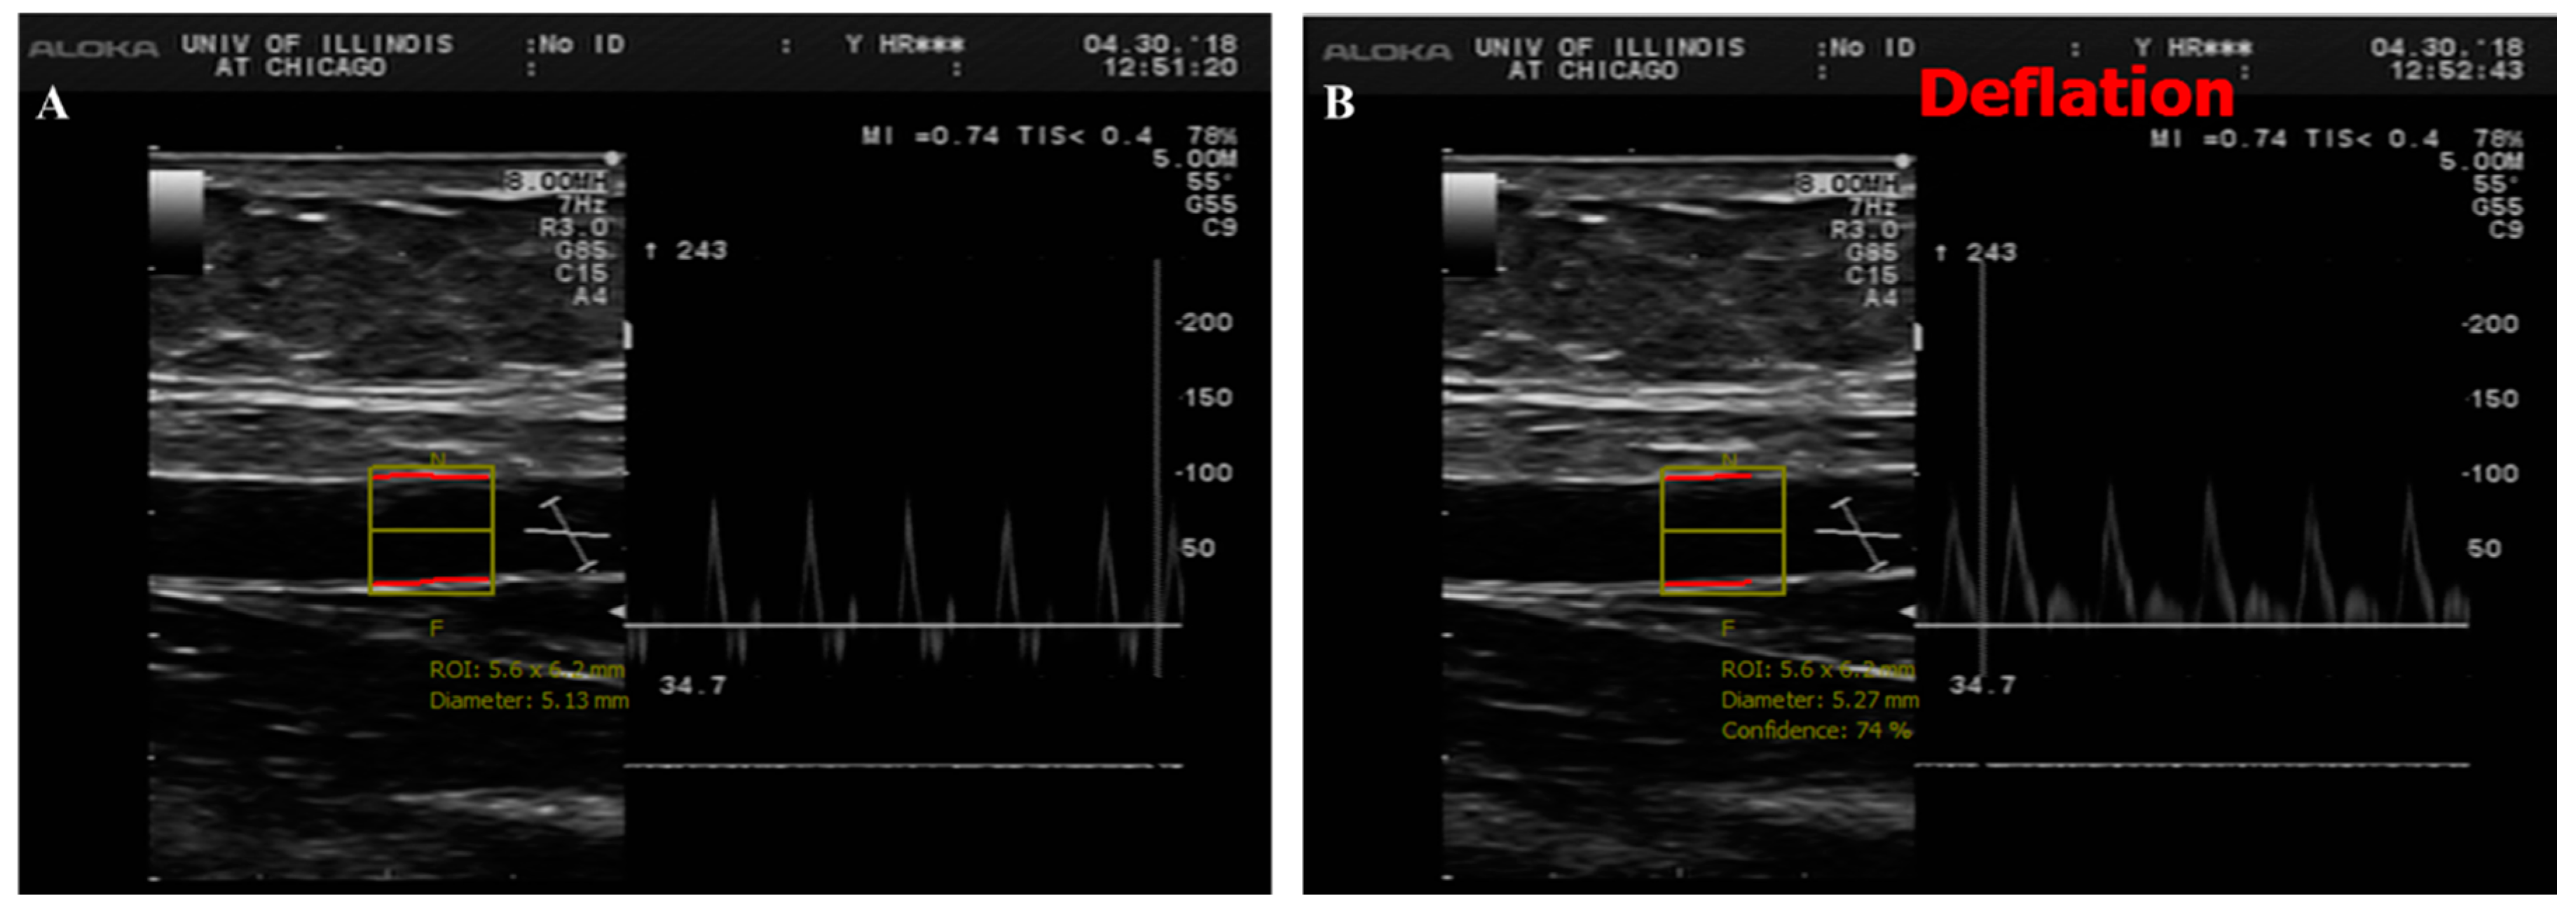

2.3. Cardiometabolic Measurements

3.3. Brachial Artery FMD